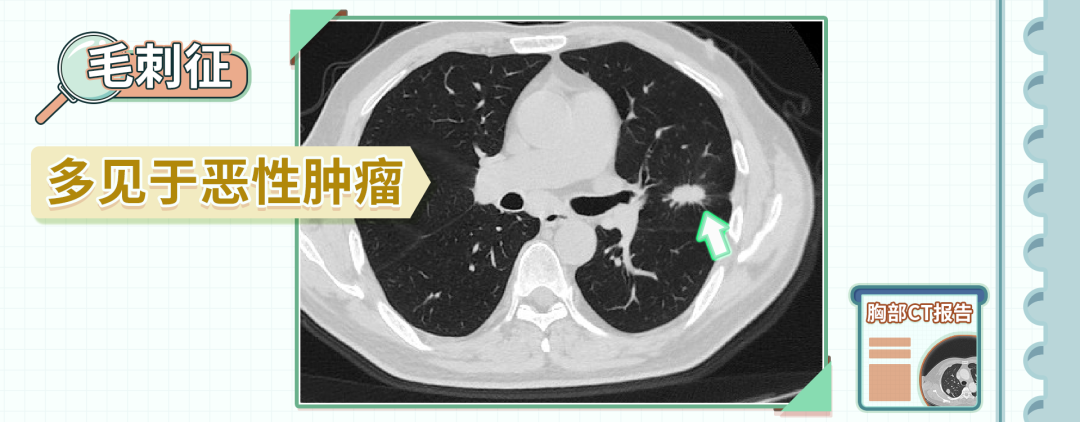

3、毛刺征

毛刺征是指结节边缘呈细线状或者是毛刷状,短而齐,呈放射状分布。

主要是由于肿瘤组织向周围浸润性生长,或者是肿瘤周围的炎性反应引起了纤维化,或者是新生血管生成造成的,一般是恶性肿瘤的征象。